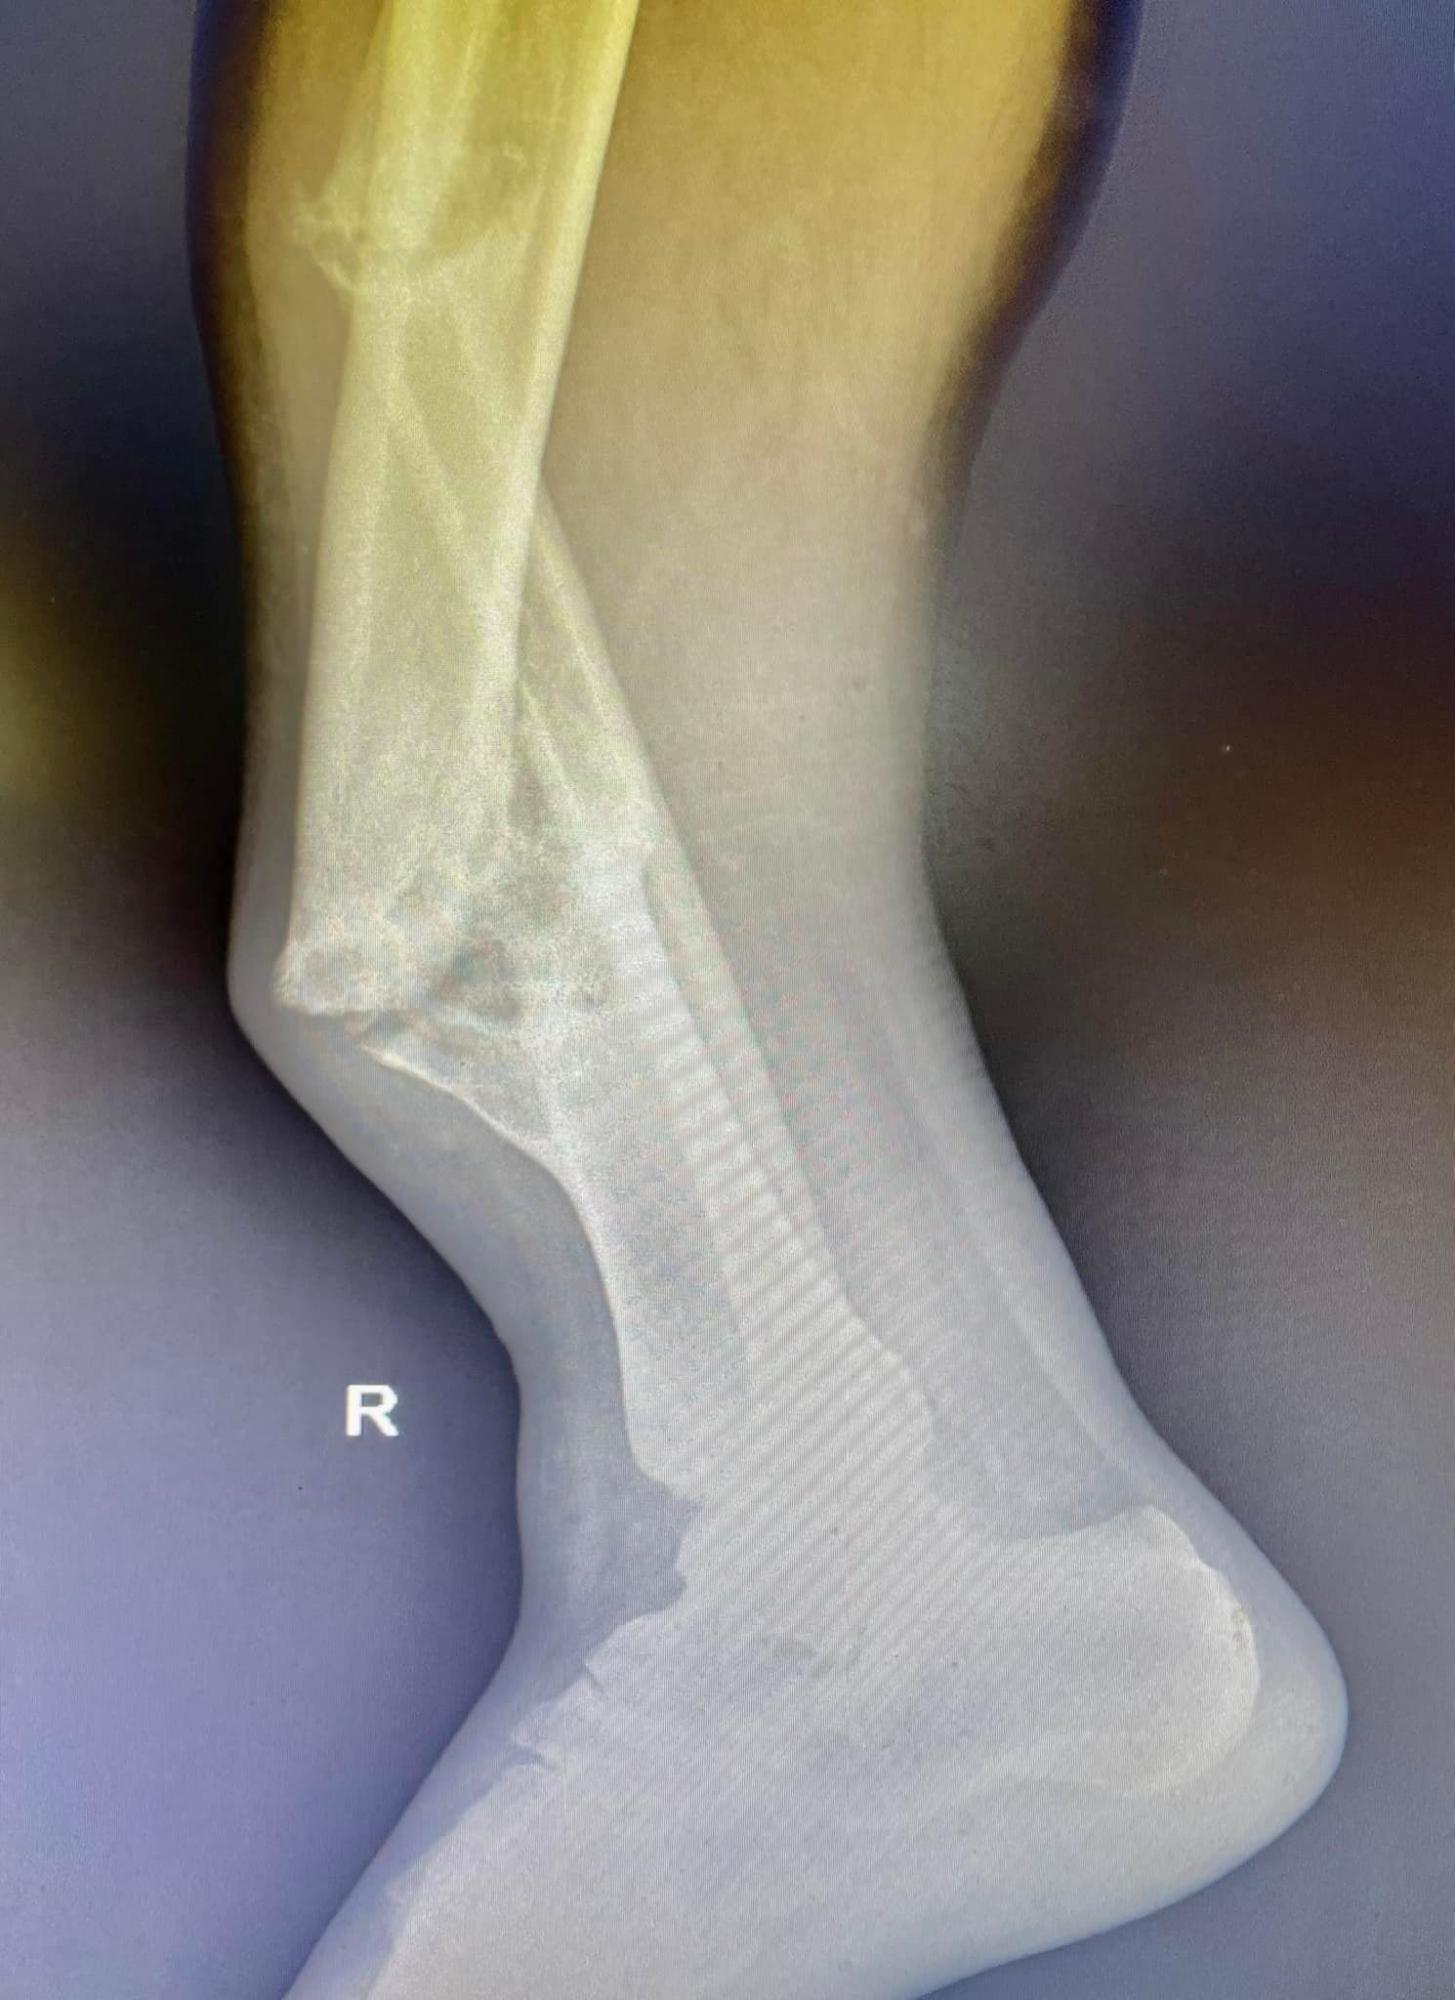

Во Львове хирурги провели операцию по удалению "фиктивного сустава" у жителя Славянска, который два года назад сломал ногу, отказался от лечения, и теперь его конечность сгибалась в разные стороны, а сам мужчина не мог ходить и уже потерял всякую надежду стать на ноги.

Как рассказали во львовском медучреждении, в 2019-м их коллеги в Славянске констатировали у Павла очень сложный перелом, который требовал операции и установки металлических конструкций. Мужчина тогда отказался.

"Полгода он лежал в гипсе, надеясь, что кости срастутся своими силами. Этого не произошло, более того - на месте перелома у него сформировался "ненастоящий сустав". Нога потеряла сопротивляемость и начала сгибаться под разными углами. Павел потерял работу", - говорится в публикации.

Врачи отделения травматологии больницы Св. Луки Первого медобъединения Львова во время операции смогли избавиться от "фиктивного сустава", выровнять ось и длину концов и установить металлические конструкции (их оплатили благотворители).

После операции еще потребуется период реабилитации, при этом врачи заявляют, что через полгода пациент "будет не просто ходить, а даже будет бегать!"

После операции для полного восстановления ноги потребуется около 6 месяцев (фото: facebook.com/1tmolviv)